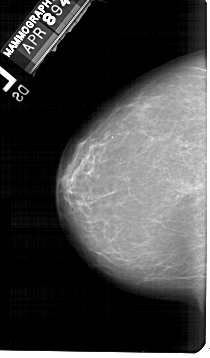

A_1548_1.LEFT_MLO

LEFT_MLO LINES 5491 PIXELS_PER_LINE 3271 BITS_PER_PIXEL 12 RESOLUTION 43.5 NON_OVERLAY